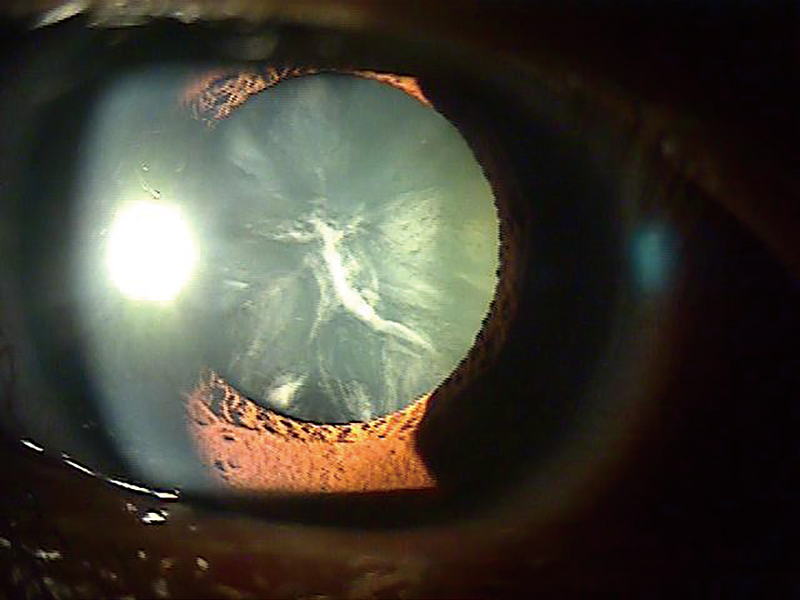

백내장은 안구 내 수정체가 혼탁해지는 질환으로, 시력 저하의 주된 원인 중 하나다. 초기에는 증상이 거의 없다가 서서히 진행되고 안개가 낀 것처럼 흐릿하게 보이거나 사물이 뿌옇게 보인다. 이에 따라 대비 감도가 떨어지고, 눈부심 및 한 눈으로 물체를 볼 때 두 개로 보이는 단안 복시가 생긴다.

백내장은 약물(산동제)을 통해 동공을 확대시킨 후 현미경 검사(세극등현미경검사)를 통해 전형적인 수정체 혼탁 정도와 위치를 확인함으로써 진단한다. 백내장은 수정체에 혼탁이 생긴 위치에 따라 피질형, 핵형, 후낭하 등 3가지 종류로 분류된다. 각각 위치에 발생한 혼탁의 상태가 어느 정도인지 단계를 평가한다.

이 중 후낭하 백내장은 수정체 후면에 있는 후낭(수정체 뒷주머니) 바로 아래에 혼탁이 발생하는 경우로 수정체 앞쪽에 발생하는 핵형 백내장이나 피질형 백내장과는 달리, 상대적으로 젊은 연령층에서 더 흔하게 발생한다. 후낭하 백내장은 시력 저하를 급격하게 일으킬 수 있는데, 이는 혼탁이 수정체의 중심부에 위치해 빛의 통과를 직접적으로 방해하기 때문이다.

백내장 수술 전 ⓒ시사저널 사진 자료